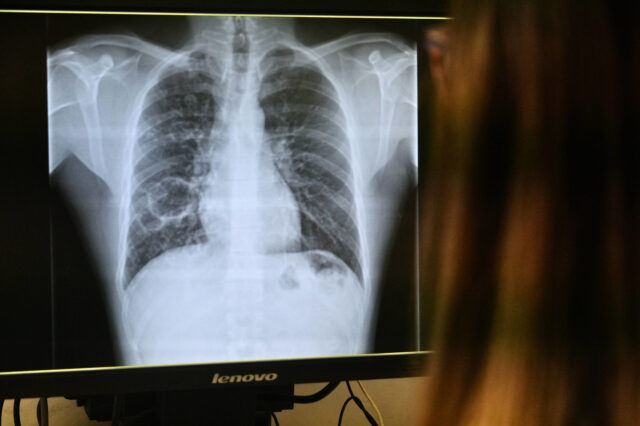

La tuberculosi és una infecció causada per un bacteri que es transmet per via aèria, però no totes les persones que contrauen la infecció arriben a presentar la malaltia.

Els ingressos per afeccions pulmonars a l’Hospital Joan XXIII es fan en règim d’aïllament fins que els pacients no són contagiosos, després de dues o tres setmanes de tractament eficaç.